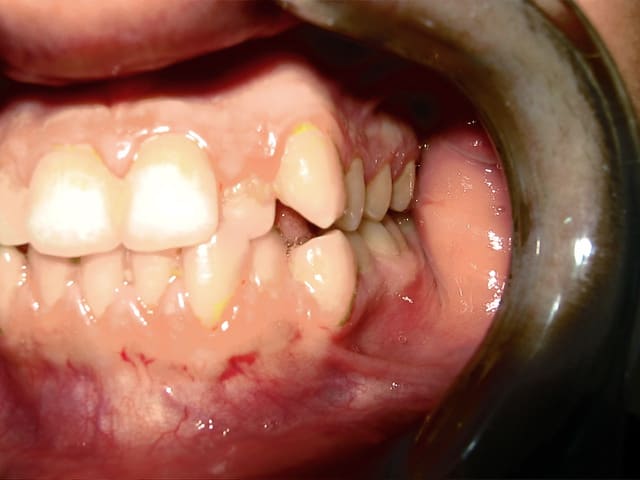

bonjour je vous presente mon cas :

j'ai recu un patient agé de 19ans , qui veut aligner ses dents.

Aprés l'etude du cas le diagnostic est le suivant :

CL1 squelettique tendance Cl3

hyperdivergent

Proalveolie sup

Normoalveolie inf avec une tendance a la retroalveolie

Prochélie

Cl3 dentaire molaire droite et gauche et Cl1 dentaire canine droite et gauche

Le plan de traitement est le suivant :

Pour resoudre le probleme d'encombrement en bas , extraction de la 34 et 44

et en haut on a une Cl3 dentaire , je penses qu'il faudrait extraire la 15 et 25 pour permettre l’avancé des molaires ?

Sinon on extrait que la 14 et 24 et les élastiques permettront cette avancé ?